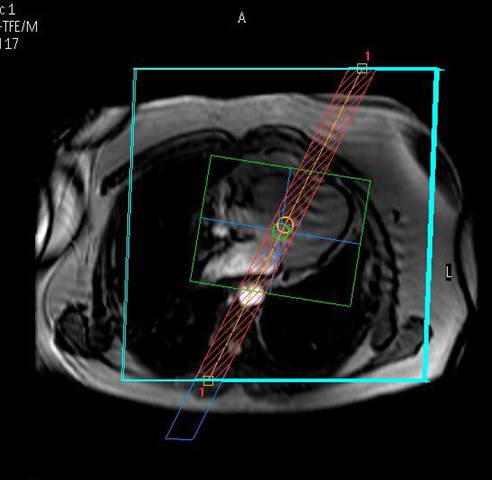

Equipment

Wir bieten modernste MRT-Diagnostik.

Ganzkörper MR System - Philips healthcare